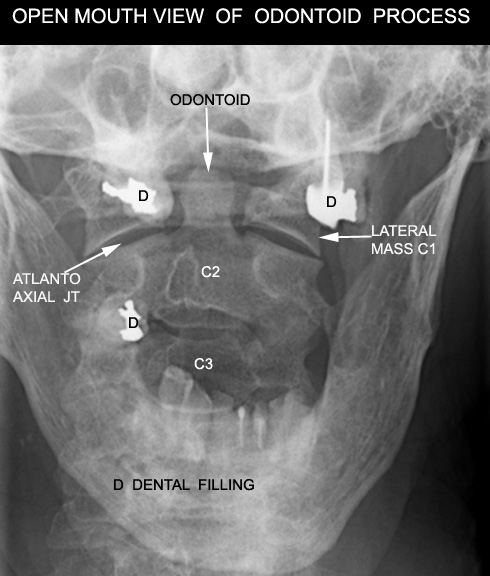

Identify the odontoid process

Click the image for labeling.